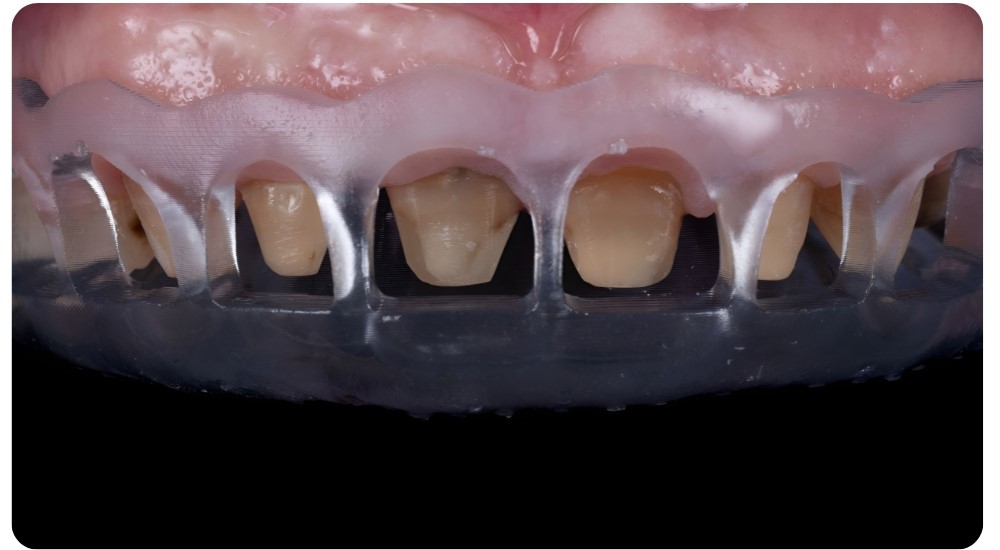

📦 3.ENTREGA

Recibirá una guía 3D impresa de alta precisión y biocompatible.